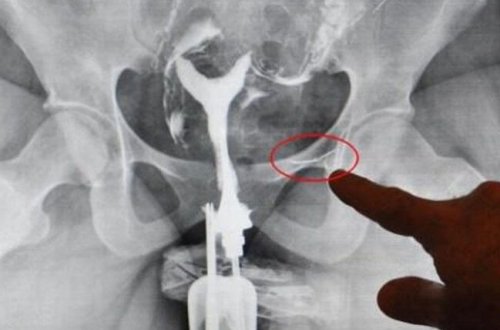

Uşağı olmayan azərbaycanlı qadın rentgenə baxanda ŞOK OLDU -

16 il əvvəl...

xəstəxanaya

iynənin

7news

üçün

sidik

tikiş

iynə

dedilər

sahibi

yapışmış

qadının

uşaq

təqdirdə

yeyəcəyim

kartof

zədələmədiyini

özünün

orqanları

çıxacağını

çoxlu